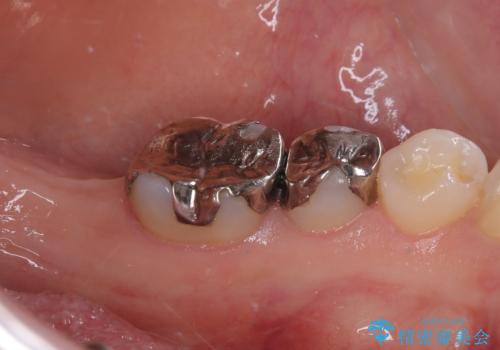

- 奥歯を抜歯してから放置しているとのことで来院された患者様です。

歯が割れて抜歯になってしまったとのことで、咬合力に抵抗できるよう、インプラントによる補綴治療を行うこととしました。

長い期間歯が欠損していた下顎奥歯に、インプラント埋入と同時に仮歯を装着すると(埋入即時荷重インプラントを行うと)、舌の付け根で仮歯を横向きに押してしまい、インプラントが脱落する危険性が高くなります。

インプラント埋入時に、装着できる状態の仮歯を用意するものの、埋入後すぐには加重させず、インプラントが無事に生着したことを確認した後に装着することで、危険を回避しつつ外科処置や痛みの少ないスムーズな治療を行うことができます。